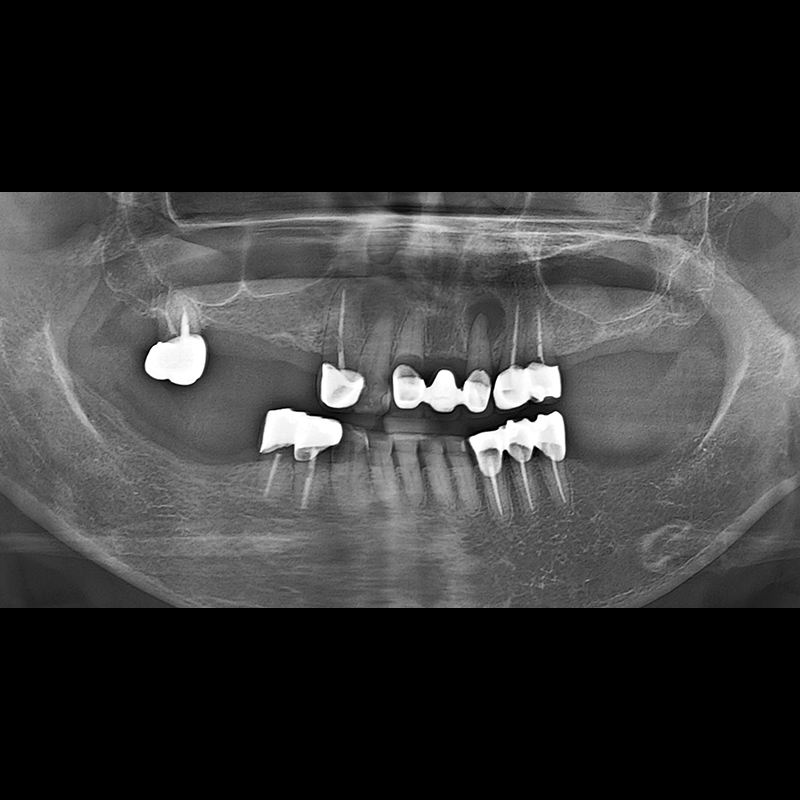

BEFORE AFTER

种植牙前后的照片 2025.05.30

在缺失的牙齿部分和难以挽救的牙齿位置植入了种植牙。